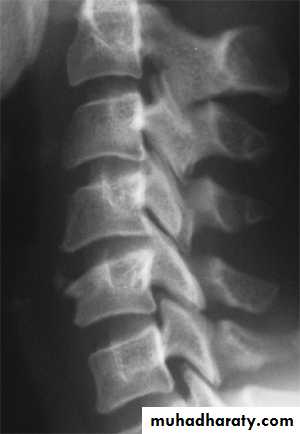

Dorsal and lumbar spine

Wedge compression fracture of a vertebral body.

Burst fracture of a vertebral body.

The thoracolumbar junction

one or more of the vertebral bodies collapses

anteriorly and becomes wedge-shaped, giving rise to a localized kyphosis.WEDGE COMPRESSION FRACTURE

The standard method of treatment may, therefore, be said to be conservative.BURST FRACTURE OF A VERTEBRAL BODY

the compression force thus acts vertically in the line of the vertebral bodies.

The intervertebral disc is forced

In the affected vertebral body, causing a comminuted bursting fracture in which fragments are driven outwards in all directions.